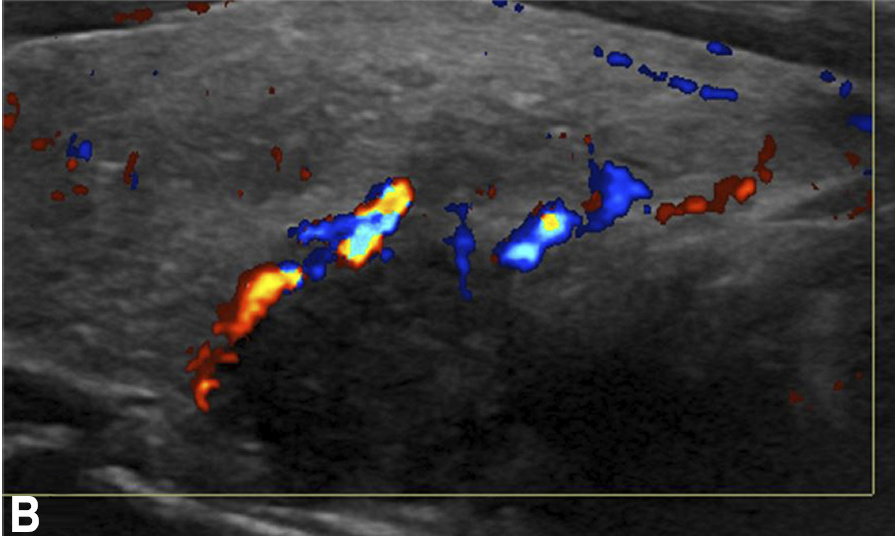

Want to help your favorite surgeons find potential parathyroid adenomas before they head to the OR? Check out our Neurographics review of unusual adenomas and expand your search/horizons! Thao Ly Gino Kevin Mathew P. Vairavan Manickam Andrés Moreno De Luca, MD, MBA, DABR @GeisingerRads #hnrad